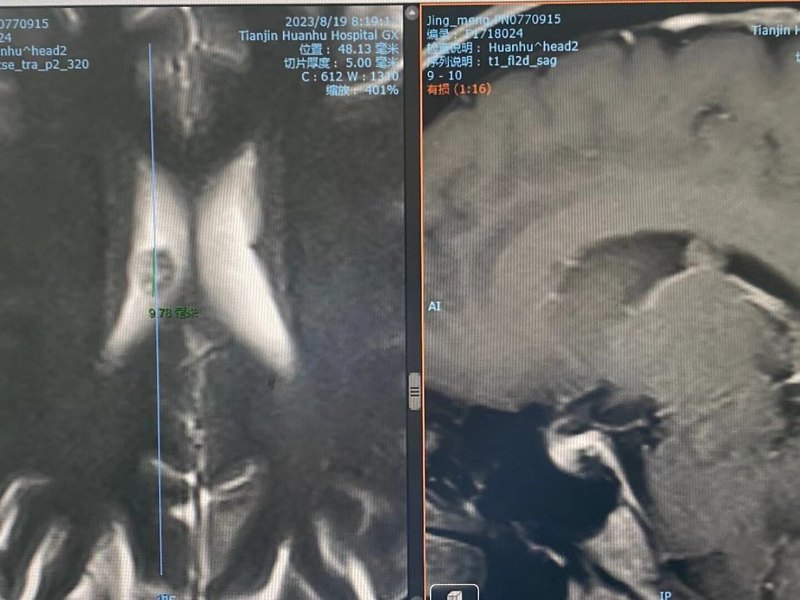

【典型病例】唐都醫(yī)院趙天智主任精準(zhǔn)全切橋小腦角神經(jīng)鞘瘤,實現(xiàn)完美保聽、保面

家住陜西安康市32歲屈先生,從2013年開始,沒有任何原因出現(xiàn)不定期右眼球內(nèi)部、右耳道內(nèi)部及舌根根部神經(jīng)性疼痛,口服卡馬西平緩解疼痛,劑量一天一次,一次一片,用藥后疼痛癥狀有所緩解,由于只是間斷性疼痛,就一直沒有放在心上,未重視。也沒有從來查到準(zhǔn)確的病因,直到2020年11月份,通過查詢、了解到唐都醫(yī)院神經(jīng)外科趙天智主任很擅長顱底腫瘤的治療,在不確定病因的前提下,慕名到趙天智主任門診就診,通過頭顱MRI結(jié)果提示:“右側(cè)橋小腦角、頸靜脈孔區(qū)占位病變”,屬于神經(jīng)鞘瘤,需要手術(shù)治療。趙天智主任介紹:從術(shù)前頭顱MRI閱片可以看出,患者的腫瘤位于右側(cè)橋小腦角,頸靜脈孔區(qū),與周圍神經(jīng)關(guān)系密切,增加手術(shù)治療難度,術(shù)中如何徹底切除神經(jīng),并最大限度保留神經(jīng)功能成為這次手術(shù)的難點。術(shù)前,趙天智主任及團隊進(jìn)行了詳細(xì)的術(shù)前討論,制定手術(shù)方案如下:精準(zhǔn)定位腫瘤位置,采取右側(cè)乙狀竇后入路切除右側(cè)橋小腦角、頸靜脈孔區(qū)腫瘤,同時避免對周圍面聽神經(jīng)、三叉神經(jīng)、外展神經(jīng)、后組顱神經(jīng)及腦干損傷,切除完畢后嚴(yán)密縫合并修復(fù)硬腦膜缺損。2022年11月16日,趙天智主任歷時12個小時,經(jīng)過精準(zhǔn)分離、全部切除腫瘤,并對腦膜進(jìn)行了仔細(xì)重建(從而起到對大腦的保護(hù)和防止腦脊液漏)。到現(xiàn)在術(shù)后9個月,對患者的生活各方面沒有受到影響,聽神經(jīng)、面部神經(jīng)都完美保留。神經(jīng)鞘瘤最常見于顱內(nèi),除此之外,還可以見于脊神經(jīng),特別是椎管內(nèi)。無論是顱內(nèi)神經(jīng)鞘瘤,還是椎管內(nèi)神經(jīng)鞘瘤,它的具體病因還不是十分清楚。一般神經(jīng)鞘瘤是因為神經(jīng)表面的Schwann細(xì)胞增殖形成的一種腫瘤,大多數(shù)的神經(jīng)鞘瘤屬于良性的腫瘤(就是神經(jīng)表面鞘膜的細(xì)胞異常增殖所形成的一種良性腫瘤)。臨床中,對于神經(jīng)鞘瘤的治療首選手術(shù)治療,其治療原則是在保留脊髓和神經(jīng)功能的同時盡可能完全切除腫瘤。一般來說在神經(jīng)外科手術(shù)中,對于椎管內(nèi)神經(jīng)鞘瘤,一般采取中間的方法,有必要在手術(shù)過程中盡可能多地識別帶有腫瘤的神經(jīng)和附著于腫瘤表面的正常神經(jīng),有時難以分離腫瘤神經(jīng),需要將神經(jīng)根一起移除。手術(shù)后患者可能暫時出現(xiàn)局部麻木。通過手術(shù)切除,大多數(shù)神經(jīng)鞘瘤可以治愈。